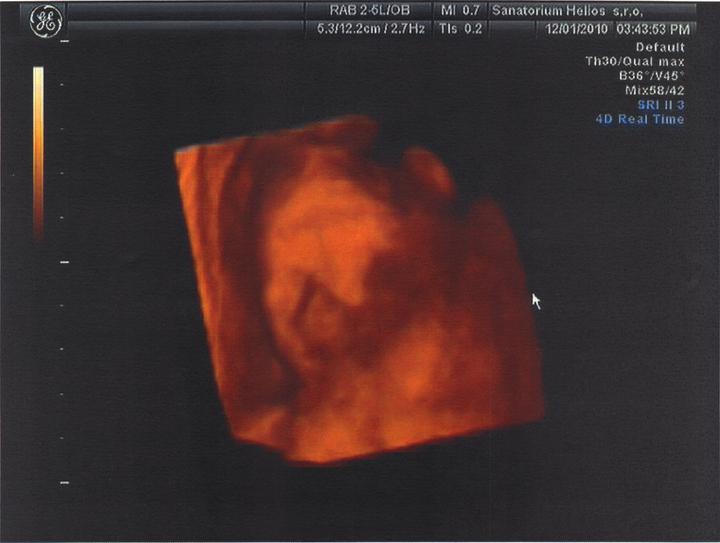

Jsme zpátky z dovolené, prcek v bříšku ani moc nezlobil🙂